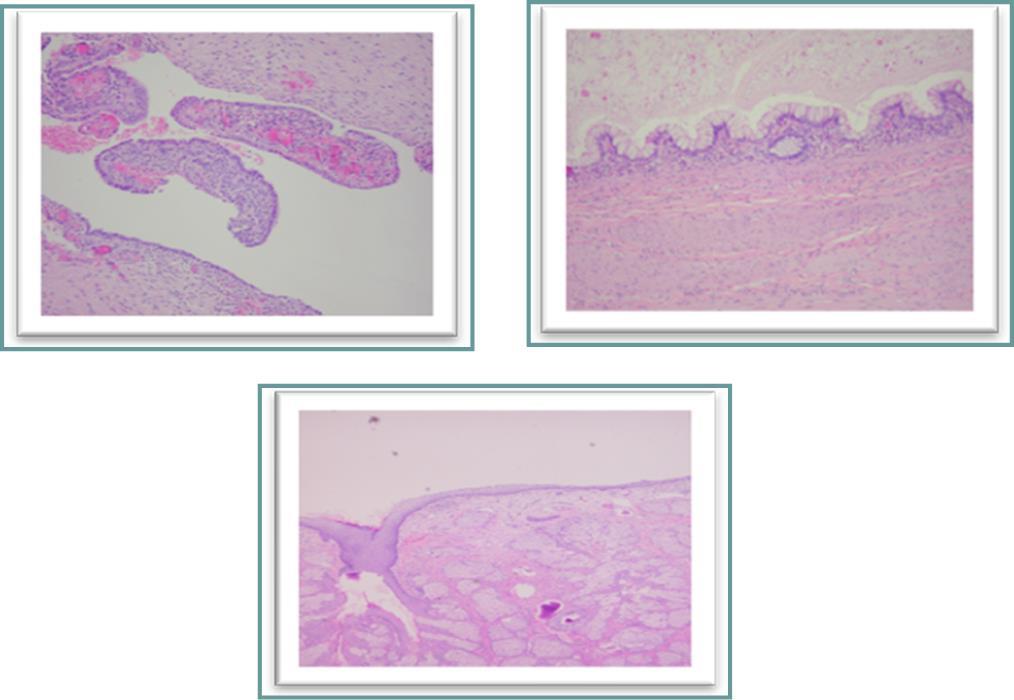

Figure 4(a, b, c).Histological examination. a, cyst lined by endometrial epithelium overcoming its endometrial stroma corresponding to an endometriosis cyst. b, a portion of the cystic mature teratoma lined with intestinal-type mucosa. c, skin surface-like structure with many sebaceous glands found on another part of the cyst.